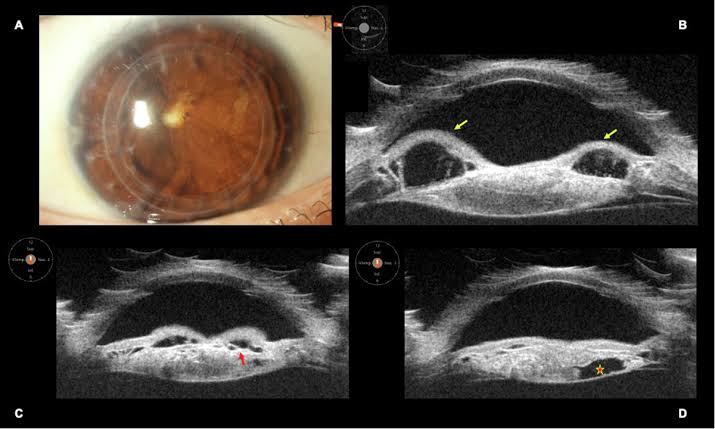

डोळ्याची सोनोग्राफी

डोळ्याची सोनोग्राफी (Ocular Ultrasound) म्हणजे अल्ट्रासाऊंड तंत्रज्ञानाच्या मदतीने डोळ्याच्या आतील रचना तपासण्याची सुरक्षित व वेदनारहित प्रक्रिया. यात उच्च वारंवारतेच्या ध्वनिलहरी वापरून डोळ्याचा मागचा भाग, रेटिना, व्हिट्रियस, ऑप्टिक नर्व्ह व डोळ्याभोवतीच्या संरचना स्पष्ट दिसतात.

या तपासणीची गरज मोतीबिंदूमुळे डोळ्याची पारदर्शकता कमी झालेली असताना, रेटिनाचे आजार, डोळ्यातील गाठी, रक्तस्राव, डिटॅचमेंट किंवा दुखापत ओळखण्यासाठी भासते. याचे फायदे म्हणजे अचूक निदान मिळणे, योग्य उपचारयोजना आखणे, शस्त्रक्रियेपूर्वी डोळ्याची स्थिती समजणे व गुंतागुंत टाळणे. ही प्रक्रिया सुरक्षित, जलद व सर्व वयोगटातील रुग्णांसाठी उपयुक्त आहे.